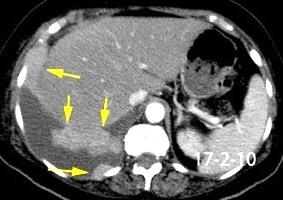

Absceso secundario a perforación de carcinoma. 3-4%. En flexura esplénica puede tener absceso subfrénico o empiema.

Empiema pleural secundario a carcinoma de la flexura esplénica (masa visible)

Lian R et al. Empyema caused by a colopleural fistula. Medicine (Baltimore) 2017/Osada T,, et al. Thoracic empyema associated with recurrent colon cancer: report of a case and review of the literature. Dis Colon Rectum 2001

Colecciones “inflamatorias” abdominales llegan al tórax vía el hiato esofágico o por vía transdiafragmática

Afectación transdiafragmática: 5,6-43,7% de quistes hepáticos. “Área desnuda” del hígado.

Panda A et al. “Straddling Across Boundaries”. Thoracoabdominal Lesions: Spectrum and Pattern Approach. Curr Probl Diagn Radiol. 2015 Área desnuda. El hígado en contacto directo con el tendón central del diafragma. Contiene el hiato de VCI.